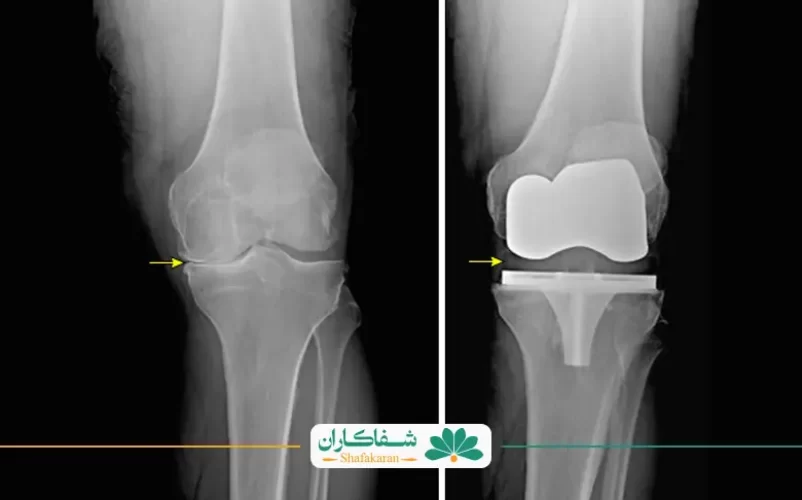

قبل ازعمل تعویض مفصل زانو، افراد مبتلا به مشکلات مفصل زانو معمولا با درد شدید، محدودیت در حرکت، و کاهش توانایی راه رفتن روزمره روبرو هستند. درد زانو میتواند عملکرد حرکتی فرد را تا حد زیادی محدود کند و به تدریج به عدم توانایی در انجام فعالیتهای روزمره منجر شود. عمل تعویض مفصل زانو اغلب به عنوان آخرین راه حل برای افراد با آرتروز شدید زانو در نظر گرفته میشود.

پس از جراحی، اثرات مثبت به سرعت قابل مشاهده هستند. انواع درد زانو به شدت کاهش یافته و در بسیاری از موارد از بین میرود. توانایی حرکتی بهبود یافته و افراد میتوانند به طور آزادتر و بدون درد راه بروند و راه رفتن و قبل و بعد از عمل مفصل زانو بهبود و پیشرفت قابل توجهی میکند.

در نتیجه، عمل تعویض مفصل زانو نه تنها به بهبود درد و محدودیتهای حرکتی منجر میشود بلکه کیفیت زندگی را نیز به شدت افزایش میدهد. این تفاوتها بیانگر اهمیت بالینی و اجتماعی این جراحی برای افراد مبتلا به مشکلات مفصل زانو میباشند و به آنها امکان بازگشت به زندگی فعال و بهتر را میدهند.